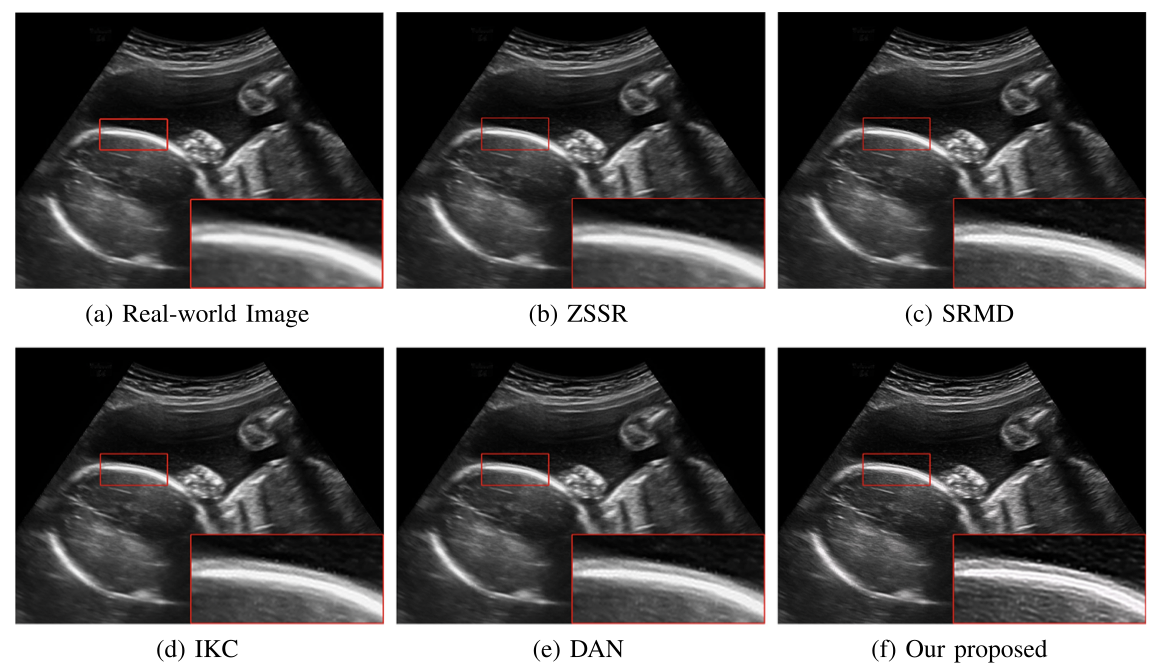

对于超声临床诊断而言,超声影像超分辨(ultrasound image super-resolution)可以提高超声成像质量,从而提高疾病诊断的准确性。但由于传感设备和传输介质的差异,实际场景中超声成像其退化模糊过程是未知且不可控的。为了解决未知退化场景超声医学影像准确超分辨的难题,团队提出了一种有效的基于退化模糊自估计且结合渐进残差学习和记忆提升机制的超声影像盲超分方法,初步实现了真实场景超声影像准确超分辨。相关研究成果发表在人工智能、计算机医学信息交叉领域一区TOP期刊《IEEE Journal of Biomedical and Health Informatics》(IF: 7.7)。我校为论文第一完成单位,计算机学院刘恒教授、硕士生刘建勇分别为论文第一、第二作者。

(真实场景超声影像盲超分效果对比图)